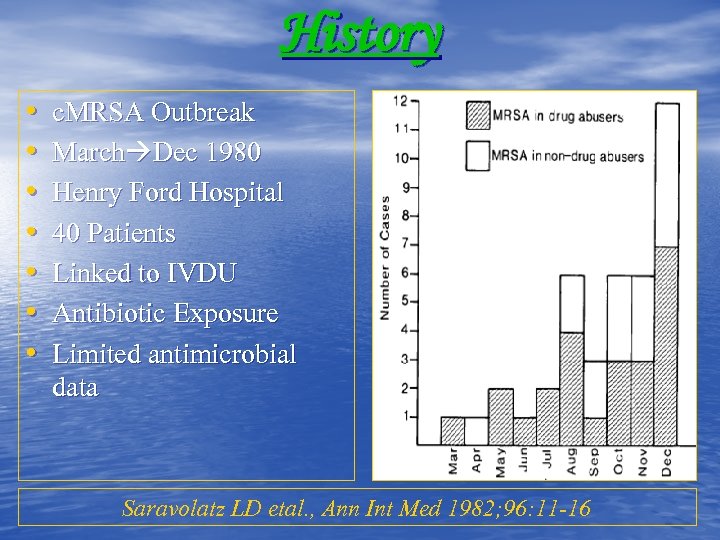

History • • c. MRSA Outbreak March Dec 1980 Henry Ford Hospital 40 Patients Linked to IVDU Antibiotic Exposure Limited antimicrobial data Saravolatz LD etal. , Ann Int Med 1982; 96: 11 -16

History • • c. MRSA Outbreak March Dec 1980 Henry Ford Hospital 40 Patients Linked to IVDU Antibiotic Exposure Limited antimicrobial data Saravolatz LD etal. , Ann Int Med 1982; 96: 11 -16